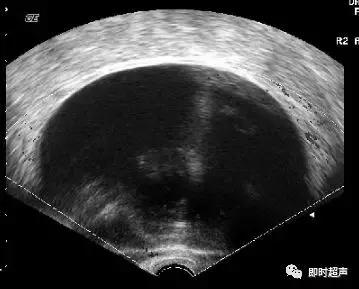

卵巢畸胎瘤声像图,因其构成成分及比例不同而表现不一,可表现为“脂液分层征”、“面团征”、“瀑布征”、“雪花征”、“线条征”、“壁上结节征”、“杂乱结构征”7种特异性声像图。

具有典型声像图的畸胎瘤较易诊断,造成误诊或漏诊者主要发生在单一组织构成的畸胎瘤,这类畸胎瘤发生率低,且超声表现与常见的由多种组织结构构成的畸胎瘤超声特点不同。因此需与卵巢子宫内膜异位囊肿、浆液性囊腺瘤、单纯性囊肿等相鉴别。

卵巢子宫内膜异位囊肿的超声表现为囊内密集点状回声,但其内也可出现带状间隔及团块状稍高回声,其与周围组织可粘连,囊壁厚而毛糙,较高回声较多沉积在中后部,呈絮状,较松散,加压探头或随访可见形态改变。患者一般有痛经病史。卵巢畸胎瘤的细密点状比内膜异位囊肿点状更细、更密、更高,团块状高回声亦更致密、更均匀、更高,且具清晰边界并常伴声影。易与囊样型和混合型卵巢畸胎瘤混淆,同时需要警惕两者并存的情况。